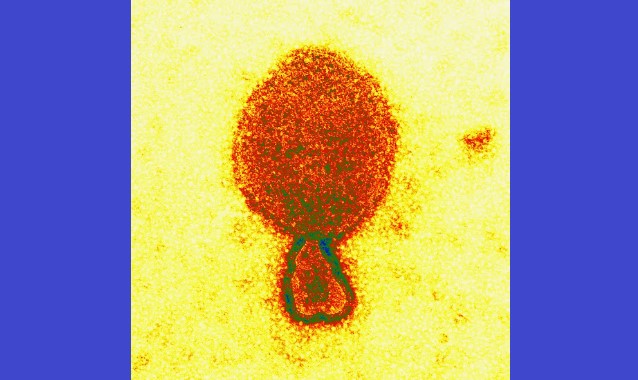

Um estudo científico feito na China e publicado na quinta-feira (4) na revista científica "New England Journal of Medicine" anunciou a detecção de um novo tipo de vírus de origem animal, o henipavírus. A doença é transmitida por morcegos frugívoros e, de acordo com a publicação, já são 35 casos confirmados por meio de amostras de saliva.

A pesquisa relata que os pacientes tiveram contato recente com animais e não há casos de transmissão de humanos para humanos. Outros tipos de henipavírus relacionados foram detectados em morcegos, roedores e musaranhos.